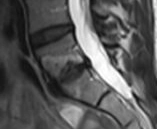

Resim 2: Lomber MRG T1 Kontrastlı

Laboratuvar: AFR normal. Rutin biyokimya normal. Brucella negatif. HLA-B27 negatif. Görüntüleme: Sakroiliyak MR olağan. Mevcut lomber MR’da L5–S1 düzeyinde spondilodiskit açısından şüpheli görünüm izlenmesi üzerine kontrastlı lomber MR istendi.

Ayırıcı tanı (Modic Tip 1 dejenerasyon? Spondilodiskit?) için sintigrafi önerildi. NSAİİ ve hareket kısıtlaması önerildi.

Kemik sintigrafisi görüldükten sonra spondilodiskit olasılığı elendi. L5-S1'deki disk lezyonu geçirilmiş bir travma ya da Schmorl nodülüne sekonder olarak artmış yoğun dejeneratif değişiklikler olarak değerlendirildi. 1600 mg/gün NSAİİ tedavisi ile kısmi fayda görüldü. Ağrı sadece sol değil sağ kasık bölgesine de ara ara yayılım gösteriyor artık ancak şiddet daha azdı. Hastaya fizyoterapi, günlük yaşam aktivitelerinde dikkat etmesi gerekenler ve kısıtlamalar önerildi ve takip planlandı.